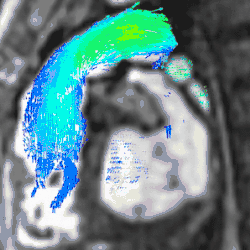

4D flow CMR

Conventional phase contrast imaging can be extended by applying flow-sensitive gradients in 3 orthogonal planes within a 3D volume throughout the cardiac cycle. Such 4D imaging encodes the velocity of flowing blood at each voxel in the volume enabling fluid dynamics to be visualised using specialist software. Applications are in complex congenital heart disease and for research into cardiovascular flow characteristics - however it is not in routine clinical use due to the complexity of post-processing and relatively long acquisition times.[26]